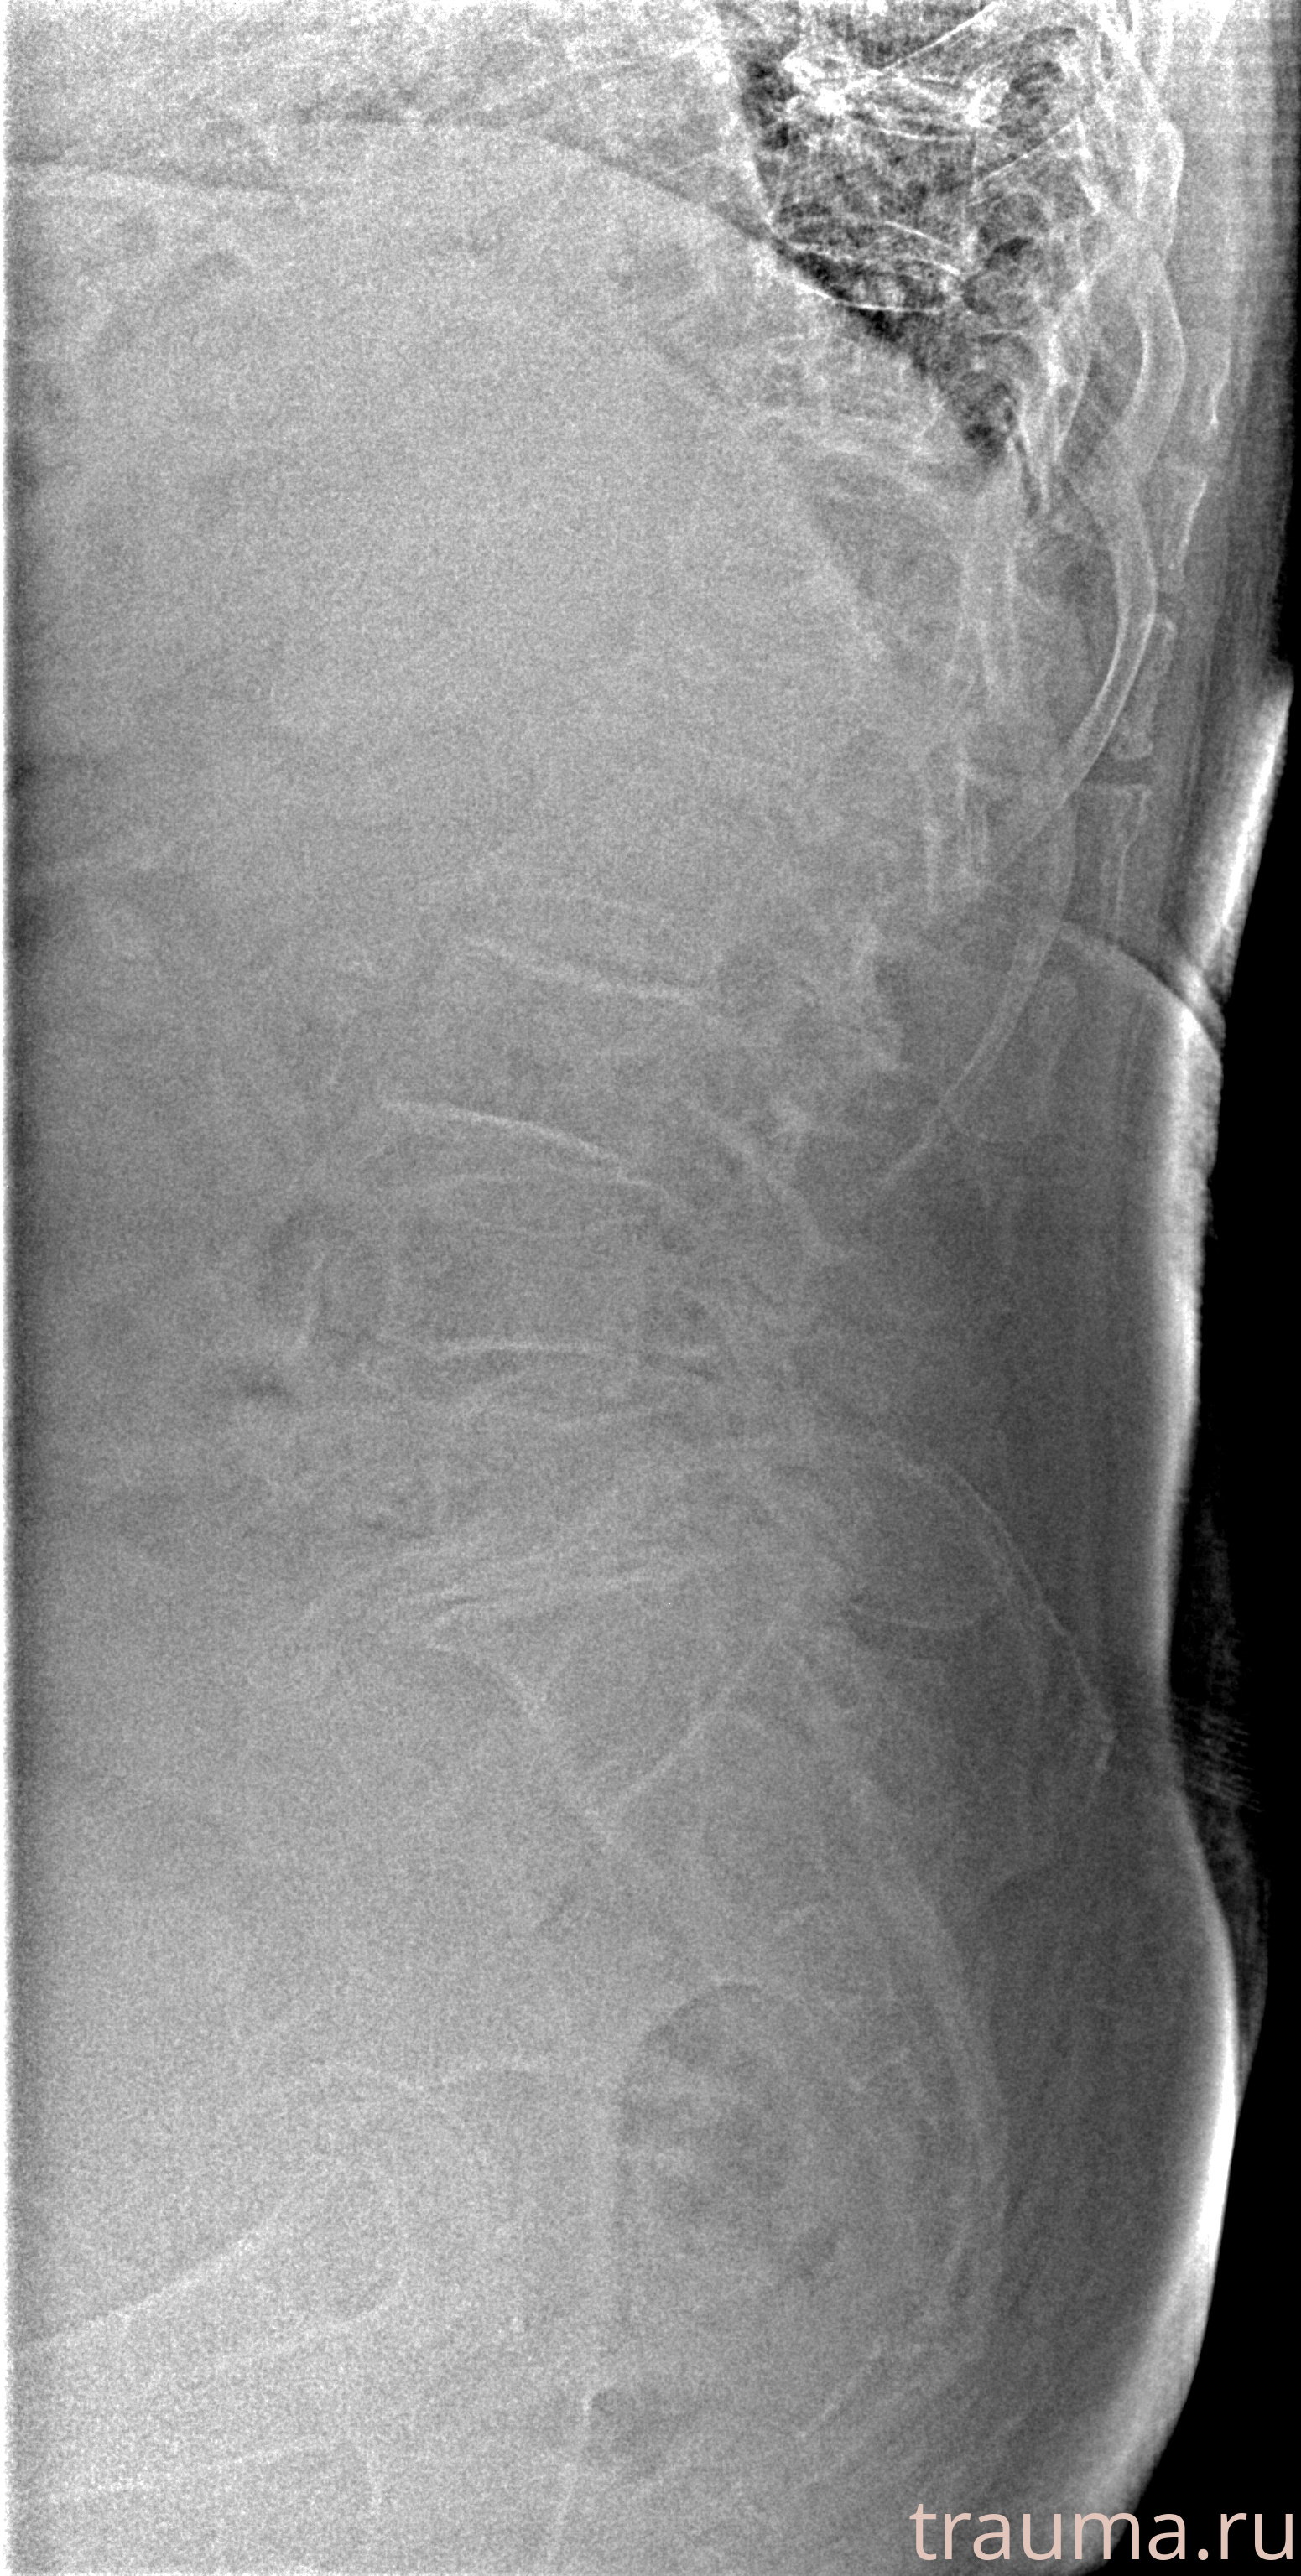

Рентгенограммы

Рентген на дому: по вашему адресу приезжает врач-рентгенолог, травматолог-ортопед с мобильным рентгеновским аппаратом, проводит диагностику травмы или заболевания, делает необходимые рентгенограммы, дает рекомендации по дальнейшему лечению. Получить качественные снимки в домашних условиях возможно благодаря уникальной методике, разработанной МосРентген Центром для института  Склифосовского